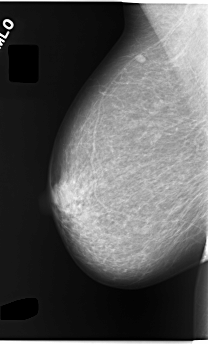

C_0055_1.RIGHT_MLO

RIGHT_MLO LINES 5848 PIXELS_PER_LINE 3528 BITS_PER_PIXEL 12 RESOLUTION 50 NON_OVERLAY